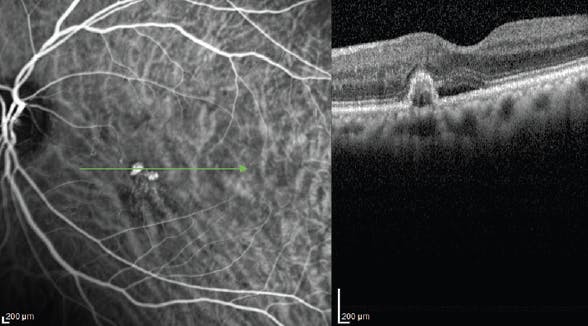

Although the current standard for the diagnosis of PCV is indocyanine green angiography (ICGA),5,6,11 it is often not available or not ordered in the routine evaluation of wet AMD. OCT is, however, readily available, making it another useful tool in this clinical scenario. The most characteristic signs of PCV on B-scan OCT are its polypoidal lesions and dilated aneurysm-shaped lesions. These appear as inverted-U-shaped elevations of the RPE with heterogeneous reflectivity (Figure 1). Because these lesions can be seen on OCT and are characteristic of PCV, B-scan OCT can be useful for diagnosing PCV in most clinical settings.

<p>Figure 1. ICGA shows large polypoidal lesions of PCV that correlate point-to-point on B-scan OCT with the inverted-U-shaped elevation of the RPE. Note the heterogeneous reflectivity of the polypoidal lesion on OCT and the serous detachment.</p>

Figure 1. ICGA shows large polypoidal lesions of PCV that correlate point-to-point on B-scan OCT with the inverted-U-shaped elevation of the RPE. Note the heterogeneous reflectivity of the polypoidal lesion on OCT and the serous detachment.

Kokame and colleagues evaluated the possibility of making a diagnosis of PCV based on OCT B-scan alone in eyes confirmed to have PCV based on ICGA.12 The polypoidal lesions were confirmed with point-to-point localization to the lesions on the ICG angiogram. B-scan OCT showed visible polypoidal lesions in 56.5% of eyes with PCV (Figure 1). The specificity was 97.7%, the positive predictive value was 97.5%, and the negative predictive value was 58.3%.